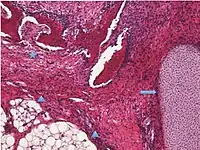

Secondary/metastatic) tumor 2%100%Usually from breast cancer, colon cancer, endometrial cancer, stomach cancer or cervical cancer.[10]